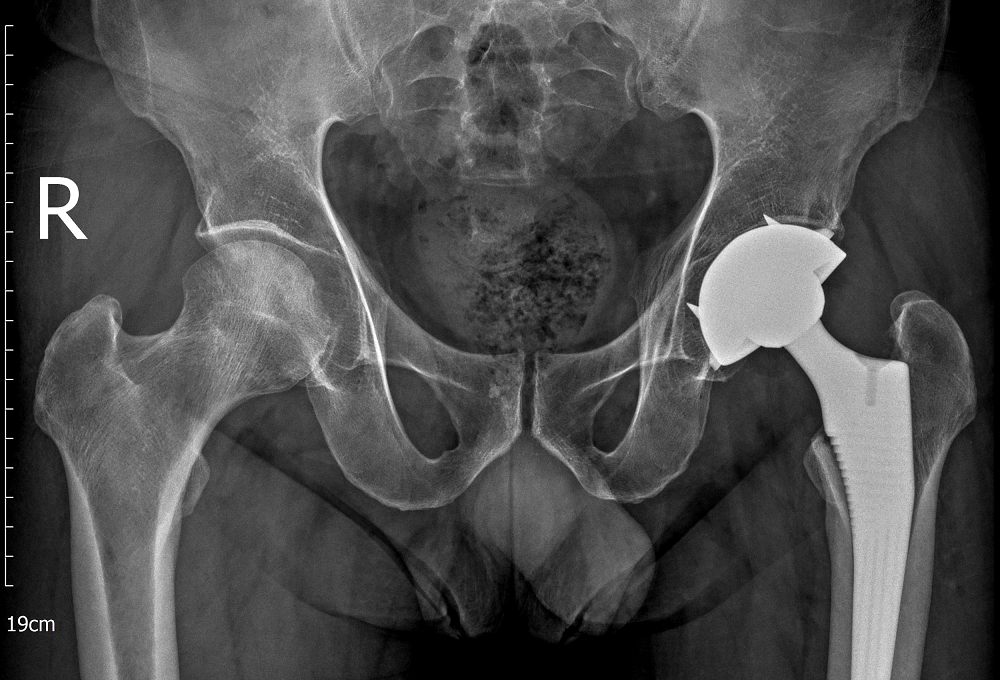

Qua thăm khám lâm sàng kết hợp chẩn đoán hình ảnh như X-quang và MRI, các bác sĩ xác định người bệnh bị hoại tử chỏm xương đùi hai bên, trong đó khớp háng bên trái đã tổn thương nặng hơn. Kết quả chẩn đoán của bác sĩ khiến người bệnh bàng hoàng.

Bệnh nhân được bác sĩ thực hiện thành công cuộc phẫu thuật thay khớp háng toàn phần bên trái

Với trường hợp này, khớp háng trái đã tiến triển đến giai đoạn nặng, không còn khả năng bảo tồn, các bác sĩ buộc phải chỉ định thay khớp háng toàn phần nhằm giảm đau, phục hồi chức năng vận động và tránh nguy cơ tàn phế cho người bệnh. Trong khi đó, khớp háng bên phải vẫn còn khả năng bảo tồn nên các bác sĩ lựa chọn phương pháp phẫu thuật giảm áp cổ xương đùi để cải thiện tuần hoàn, làm chậm quá trình hư khớp.